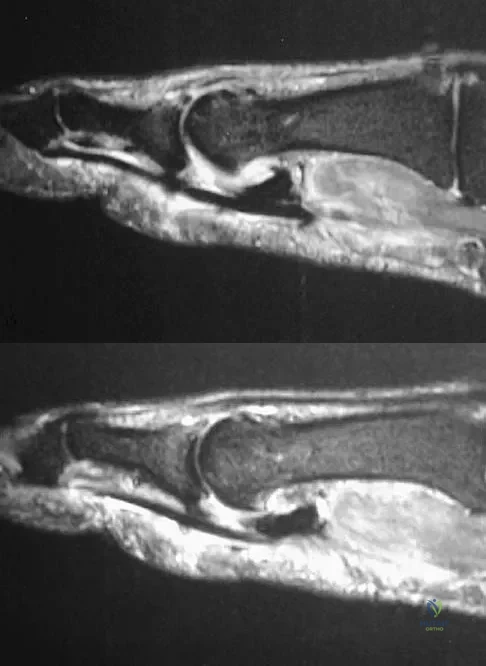

Question 93 High Yield

Figures 11a and 11b show the T2-weighted MRI scans of the lumbar spine of a 53-year-old woman who has low back and right lower extremity pain. What structure is the arrow pointing to in Figure 11a?

Detailed Explanation